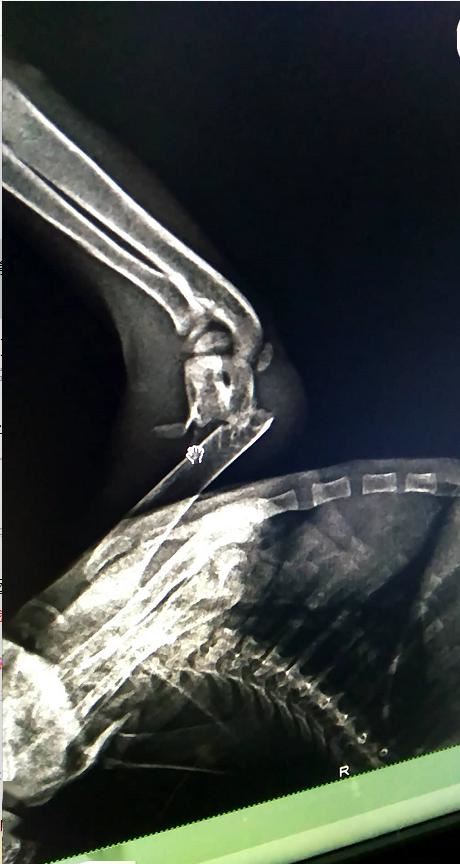

过了一夜之后,猫咪被带去医院,最让我们担心的事情还是发生了。小猫受伤的脚正是最难治疗的地方。右前肢的关节处直接折断了,而这个地方是最难处理的。比如一些猫坠楼或者出车祸,都很容易出现这种情况。对于一只成年猫来说,这个手术不是很难,可是对于刚刚满月的小猫,却是非常困难的。

小猫受伤的脚

第一个困难就是小猫的骨头太细,怕无法承受钢钉。

第二个困难就是在手术的过程中有很大风险。比如在麻醉时,由于小猫太小,可能一不小心药剂控制不好导致小猫死亡。

第三个困难就是术后的护理,也是一件非常棘手的问题。术后还可能会引起一系列继发性的病,比如最严重的夺命“猫瘟”。

又一个大困难摆在面前了,大家都很纠结,到底是该做手术给它一个光明的未来,让它将来可以像正常的猫一样,被领养,享受家的温暖......还是说采用比较稳妥的方式,给它采用外固定的治疗方式,但是效果很差,畸形愈合对它将来的步态行走都是有很大影响。